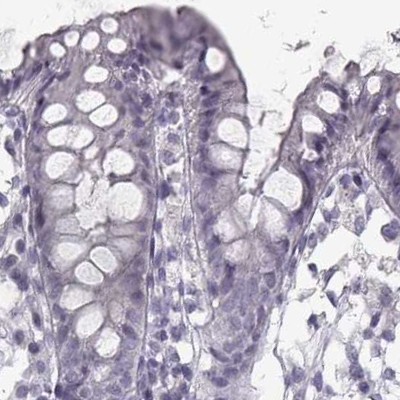

Immunohistochemistry analysis in human seminal vesicle and skeletal muscle tissues using Anti-SEMG2 antibody. Corresponding SEMG2 RNA-seq data are presented for the same tissues.